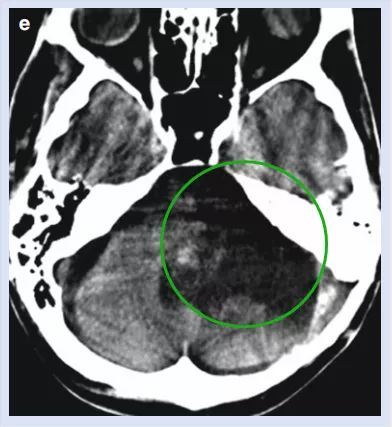

术后2周CT结果

因为患者病情复杂,术后给予延长强化治疗,身体各项功能逐渐好转,甚至可以停止使用呼吸机。他较初恶化的吞咽情况得到了好转,还移除了气管插管;平衡感和身体控制能力也得到了好转,出院时他已经能在护士的照顾下行走了。